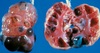

A 9-year old female spayed German Shepherd presented for extreme lethargy. Physical examination and diagnostics were consistent with a hemoabdomen.

The patient was taken to surgery and a splenic mass was found (see image). The remainder of your abdominal exploration was unremarkable. What is the most common malignant tumor of the spleen in the dog?

Answer: Hemangiosarcoma

The correct answer is hemangiosarcoma. This tumor accounts for approximately 2/3 of malignant splenic masses and will have metastasized in >90% of cases by the time they are diagnosed. Chemotherapy would be recommended for adjunct therapy after surgical removal of the spleen. Lymphoma is not as commonly found in the spleen in dogs, and you would have expected enlarged lymph nodes to be mentioned in the question. Mast cell tumors occur with some frequency in the spleen of cats but not so often in dogs. Transitional cell carcinomas are typically found in the urinary bladder, since that is where transitional cells are located.